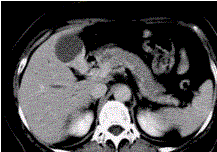

问题 患者女,50岁,右上腹痛,向肩胛部放射,伴有消瘦、乏力。查体:皮肤巩膜黄染,墨菲(Murphy)征阳性。CT示胆囊壁不规则增厚(下图)。 最可能的诊断为

选项 A.胆囊炎 B.胆囊结石 C.胆管炎 D.胆囊癌 E.胆囊腺肌症

答案 D